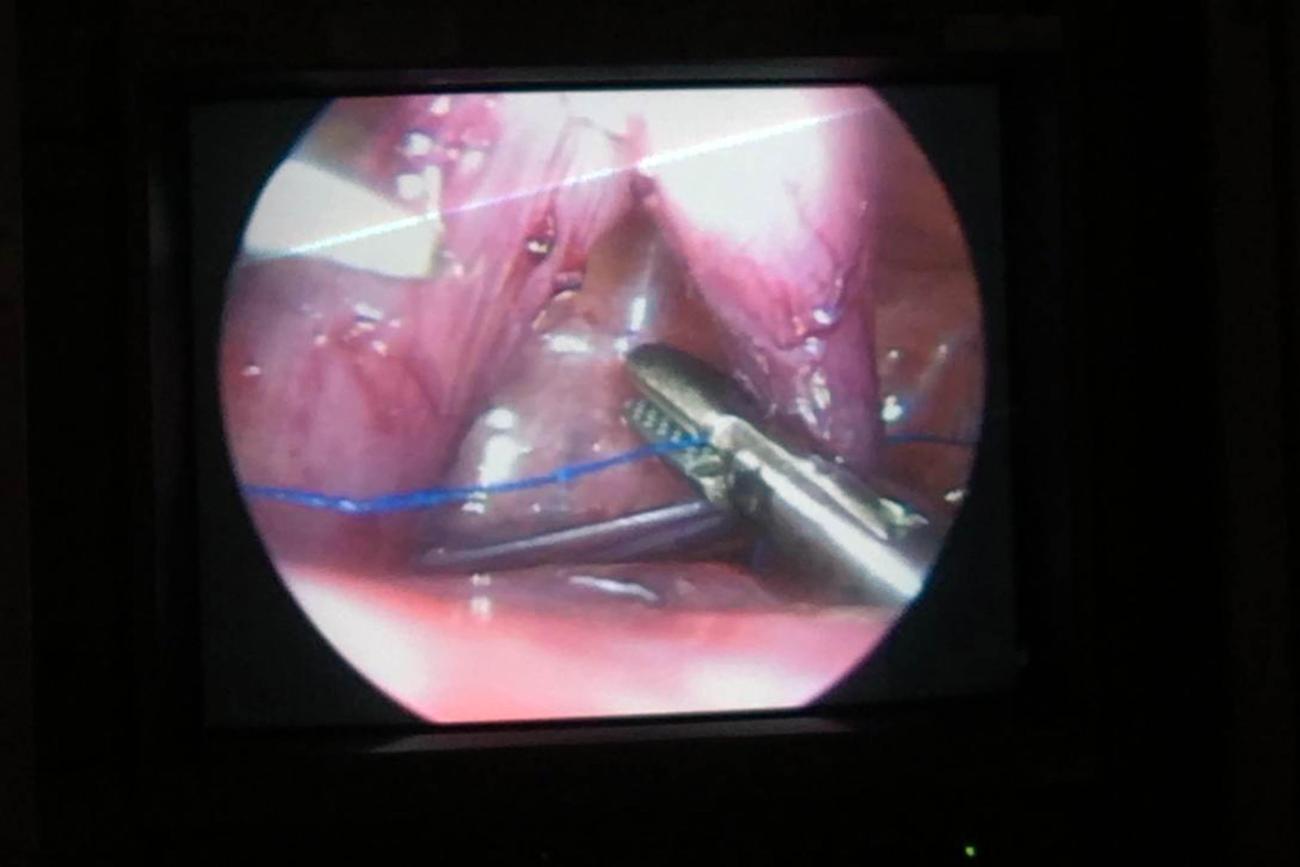

Já está em casa e se alimentando corretamente a bebê que passou pela cirurgia de videotoracoscopia (Cirurgia torácica videoassistida). Essa foi a primeira vez que a equipe médica de cirurgia pediátrica da Santa Casa realizou o procedimento. A intervenção cirúrgica foi necessária para realizar uma correção no esôfago do bebê, a criança tinha atresia de esôfago, uma má formação que o impede de se alimentar corretamente.

FOTO: ASCOM SANTA CASA

DATA: 05.02.2019

BELÉM - PARÁ